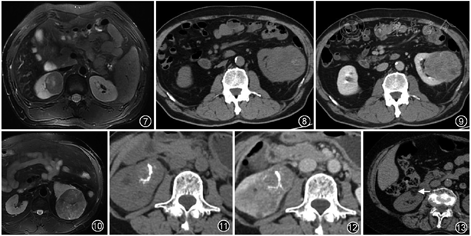

肾乳头状细胞癌CT平扫呈等及稍高密度,MRI T1WI上呈等、低信号,如含血性成分则在T2WI上呈低信号(图7)。与透明细胞癌不同,乳头状细胞癌的强化程度低,以轻度不均匀强化常见,增强图像CT值仅增加10~20 HU[3, 5, 6](图8,9)。肾乳头状细胞癌多表现为皮质期强化较低,强化程度随时间延迟可有略增高趋势,呈“缓慢升高”型。

3.肾嫌色细胞癌:占肾细胞癌的4%~8%。肿瘤呈实性,中心多位于肾髓质,呈膨胀性生长,边界清楚,可稍有分叶状。肾嫌色细胞癌的增强常较透明细胞癌均匀且强度低,但较乳头状细胞癌强化程度高。肾嫌色细胞癌的预后与乳头状肾细胞癌相似,5年生存率为80%~90%[3, 4, 5, 6]。

肾嫌色细胞癌于MRI平扫T1WI上呈等或稍低信号,T2WI呈稍低信号,近30%肿瘤中心可见星芒状或轮辐状改变(图10)。嫌色细胞癌属少血供肿瘤,皮质期多为轻中度强化,实质期肿瘤强化形式多样,多数较皮质期强化明显,且强化相对均匀(图11,12),肿瘤较小时,其密度均匀,很少出现坏死、出血和囊性变,超过38%肿瘤可出现钙化,钙化呈片状,境界可清楚或模糊(图11)。肾脏肿瘤若大于7 cm,出现均匀一致的轻度强化且伴钙化,则强烈提示为肾嫌色细胞癌[7, 8, 9]。

AML最典型的影像特征是其内的脂肪成分。因病变内含平滑肌成分,可于T2WI上呈现低信号。AML为良性肿瘤,生长缓慢,可出现“劈裂征”或“杯口征”改变(图13),即在皮质内生长的肿瘤缓慢向肾外膨胀生长,最终突破皮质并将相邻的皮质掀起或挤压所致。增强扫描AML强化不均匀,肿瘤内血管成分多明显强化,平滑肌成分也显示增强,而脂肪成分几乎不增强。约5%的AML在影像上没有明显的脂肪成分,即为少脂肪型或乏脂型AML,与肾细胞癌鉴别困难。